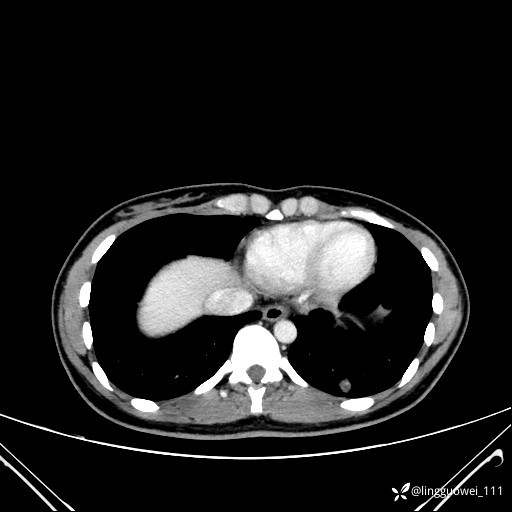

患者性别:女

患者年龄:26岁

主诉:咳嗽来诊,结节性质不明。

肺毛细血管瘤 (2)